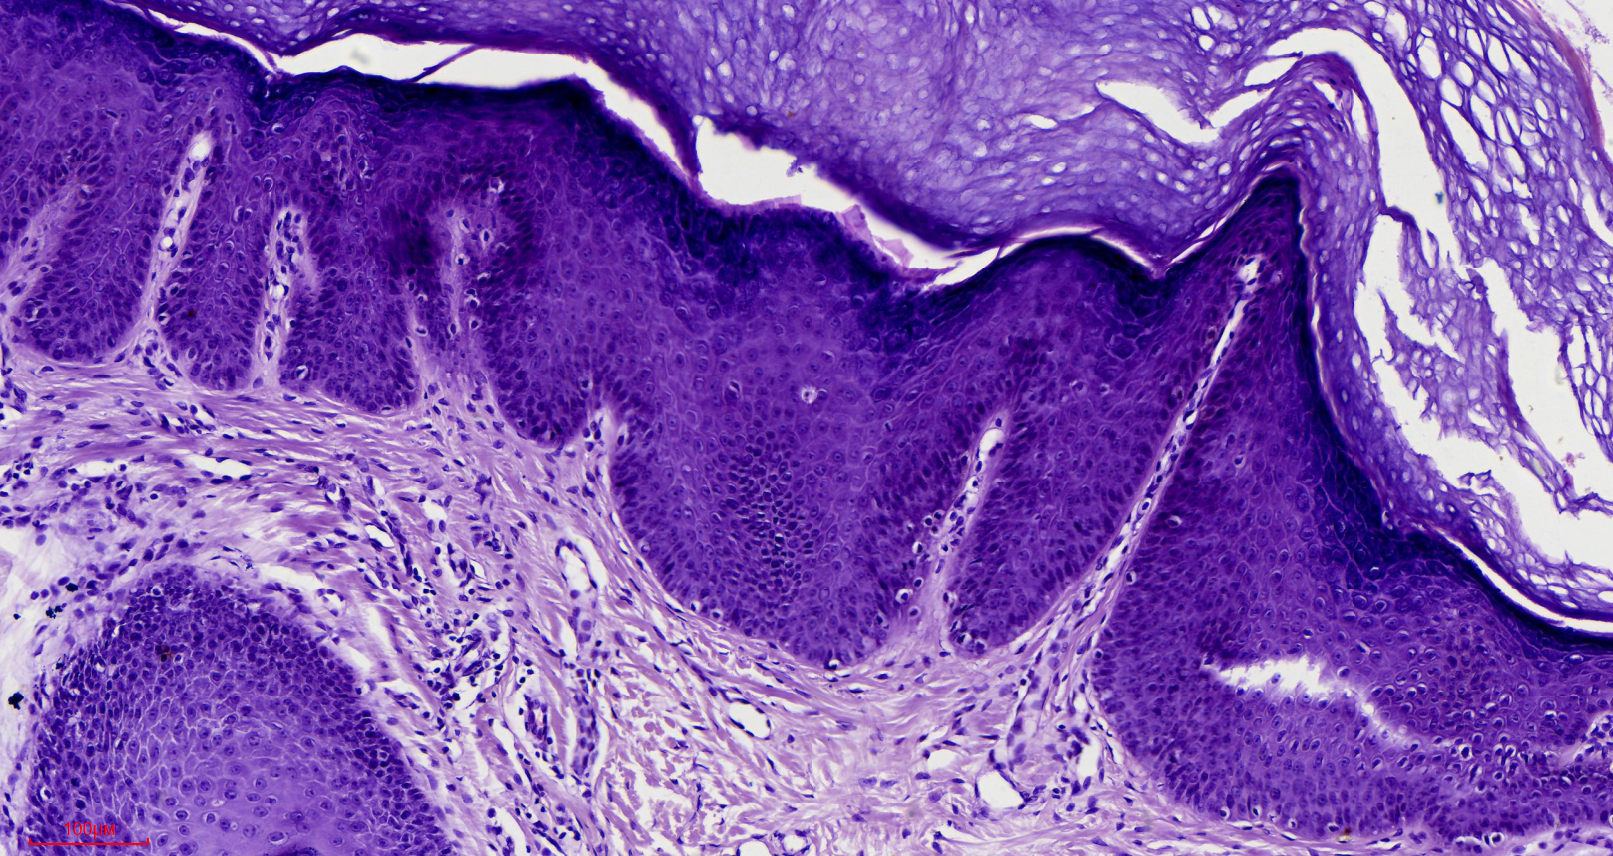

求助,请老师帮忙看看表皮有问题吗?

性别

女

年龄

16岁

临床诊断

待诊

一般病史

发现头顶包块1年

标本名称

包块

大体所见

楔形皮肤组织,2*1*0.8,皮肤表面中央可见一粗糙区面积1*1,切面质韧

毛囊痣。